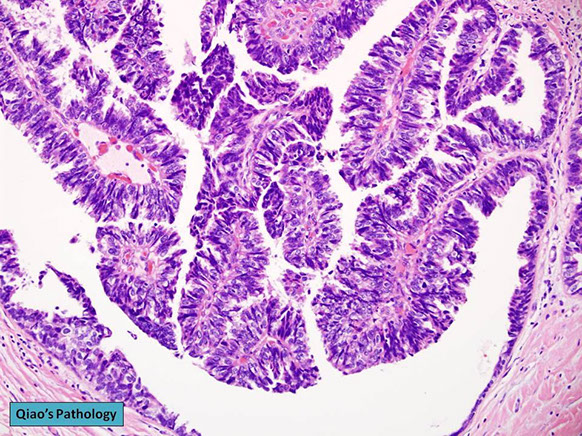

Papillary DCIS

Lesion is DCIS growing with papillary architecture, without any benign papilloma present

- have no ME layer (should be present at lesional border, or else is considered invasive), grow uniformly perpendicular to cores, have dark nuclei, delicate (less fibrotic) stroma, absent apocrine metaplasia